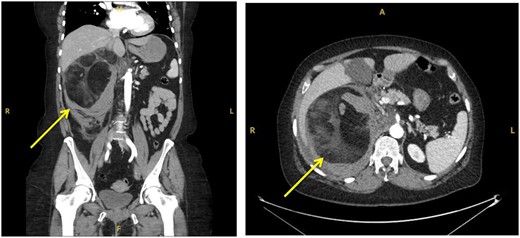

On interval CT scanning, the adrenal lesion was shown to have decreased in size (14.3×13.2 cm), likely due to reduction of intralesional haematoma, and no active haemorrhage identified (Fig. 3). There was an incidental finding of filling defects in the right lower lobe pulmonary artery. The patient was therefore re-admitted to work-up for PE. The patient was asymptomatic of venous thromboembolism. A CTPA identified bilateral segmental and sub-segmental pulmonary vessel filling defects, with no evidence of right heart strain. This therefore warranted commencement of anticoagulation; however, the patient remained at risk of re-haemorrhage of the adrenal lesion. On discussion with different relevant specialties and after counselling the patient on the risks and benefits, it was decided to commence on treatment dose Enoxaparin (low-molecular weight heparin). Due to her higher propensity of haemorrhage, the patient remained as an inpatient for close observation of signs of haemodynamic compromise. The patient remained well on Enoxaparin and was eventually discharged.

Interval CT imaging showing decrease in size of lesion and surrounding haematoma.